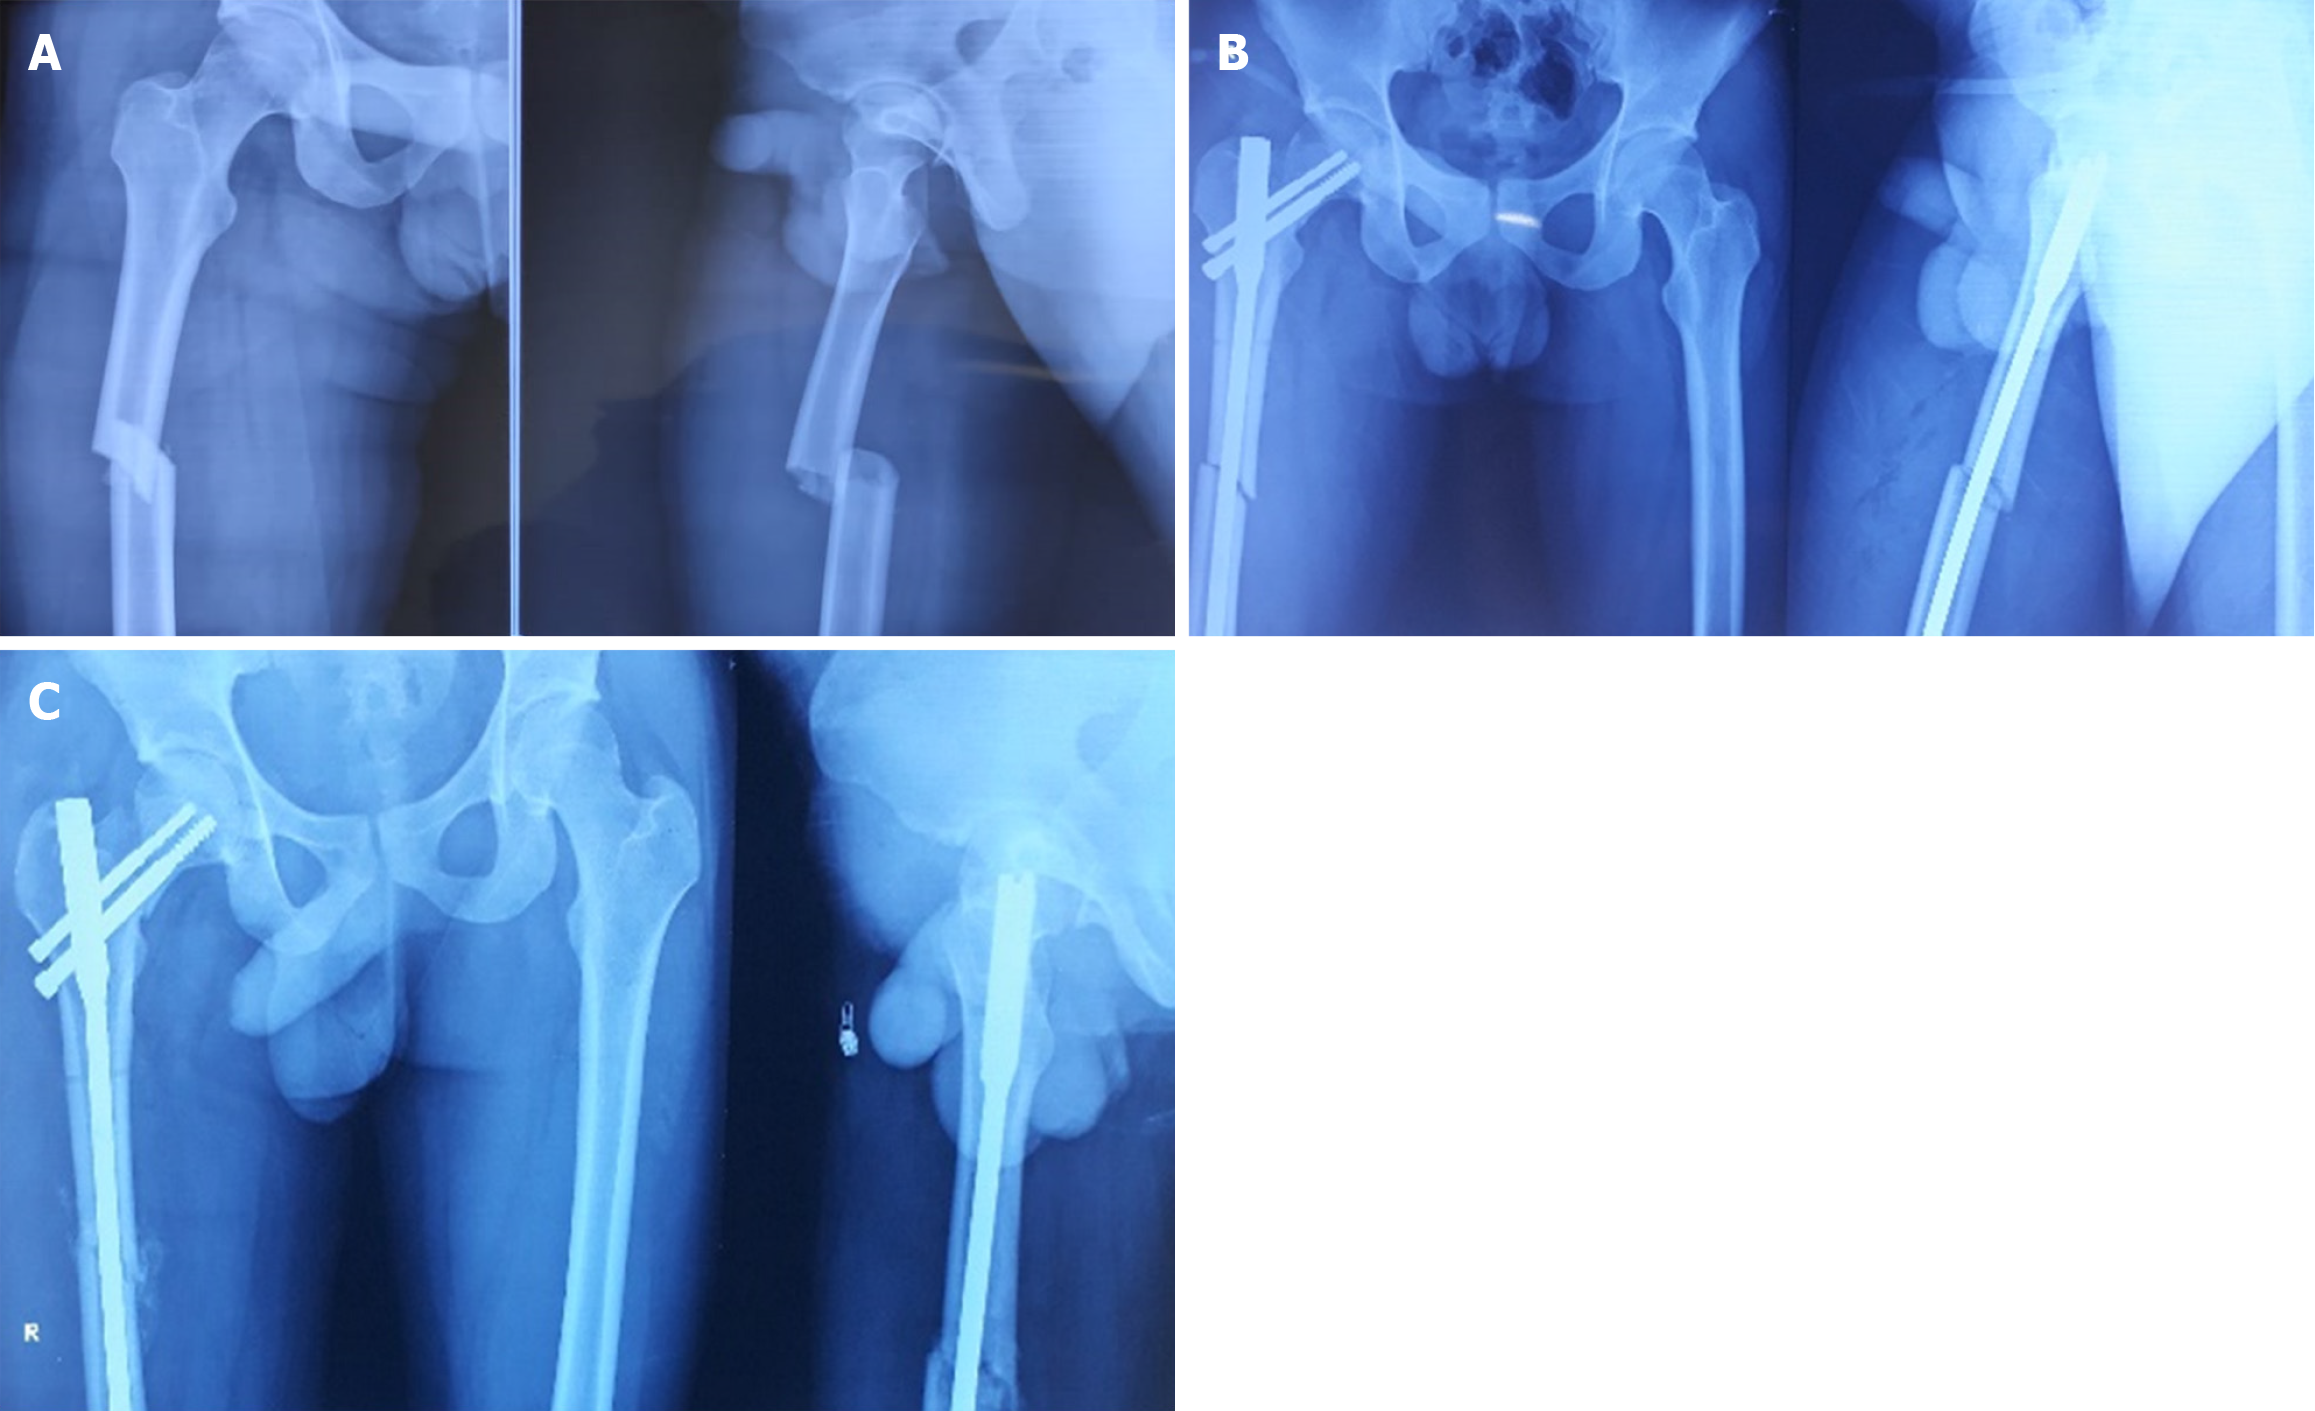

Fractures were diagnosed intraoperatively in 14 cases, immediately postoperatively in 1 case, and during follow-up (within 4 weeks) in 3 cases. The etiological breakdown included erroneous entry point (6 cases) as shown in Figure 3, inadvertent jig hammering (5 cases) as shown in Figure 4, misdirected nail manipulation (3 cases), hoop stress-related fractures (3 cases) as shown in Figure 5, and one case of unexplained origin. Intraoperative fractures were typically identified during final fluoroscopic checks, while postoperative fractures were detected on follow-up radiographs without intervening trauma Figure 6. The list of eitiologies contributing to iatrogenic fractures during femoral nailing is listed in Table 1.

Among the 18 cases, 11 were undisplaced and 7 were displaced. Fixation methods included long proximal femoral nails (10 cases), cannulated cancellous screws (6 cases) as shown in Figure 6, bipolar hemiarthroplasty (1 case) as shown in Figure 7, and dual implant technique with limited contact dynamic compression plate (1 case) as shown in Figure 7. The “miss-the-nail” technique was employed in cases where the interlock nail remained in situ and removal was deemed risky due to potential displacement as shown in Figure 5 and Table 2.

| Intraoperative | 14 | Long PFN, CCS | 110 ± 15 | 12/14 (85.7) |

| Delayed post-operation (≤ 4 weeks) | 3 | CCS, hemiarthroplasty | 145 ± 20 | 1/3 (33.3) |

The iatrogenic neck fracture diagnosed before the complete insertion of interlock nail should be managed with long proximal femoral nail[4]. However, once the interlock nail has been fully inserted, the diagnosed neck fracture should be fixed as early as possible using the cannulated cancellous screw since removing the nail may displace the neck fracture and increase the risk of avascular necrosis of the head. Also, the use of the long proximal femoral nail in this scenario may results in significant malreduction of the neck fracture[27]. It has been found that postoperatively diagnosed iatrogenic neck femur fracture can be managed effectively with cannulated cancellous screws but delay in such diagnosis adversely affect the outcome[6,27]. Doing proximal femur nailing in such cases increases the operative time, blood loss, infection rate and may also disturb the primary shaft fracture union while removing the interlocking nail. We must consider the various options of rendezvous dual implanting techniques based upon the fracture pattern, the time elapsed since fracture, and patient risk factors[22].